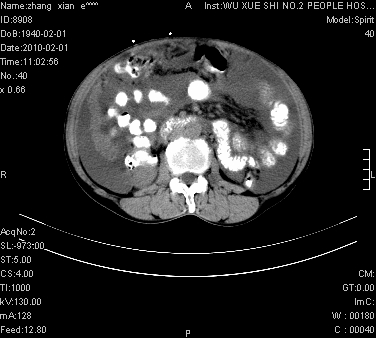

标题: CT24434:70岁 女 腹胀,腹水原因待查 [打印本页]

标题: CT24434:70岁 女 腹胀,腹水原因待查

大量腹水,脾脏囊性占位,子宫颈占位,右侧腹股沟淋巴结肿大,建议+c,先查妇科。

腹盆腔大量积液,子宫增大,子宫颈增大外形不规则,内见低密度影,膀胱后壁显示不清,右腹股沟肿大淋巴结,脾脏囊性占位,子宫颈占位,子宫颈癌?建议增强。

考虑:1、腹膜转移,大量腹水;

2、脾占位性病变;

3、左侧卵巢占位性病变,建议增强进一步检查。